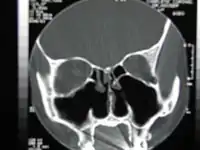

![]() Tomografía computarizada de la nariz después de una turbinectomía bilateral total. | ||